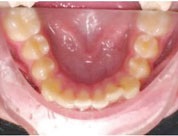

Figs. 3a-g: Initial records.